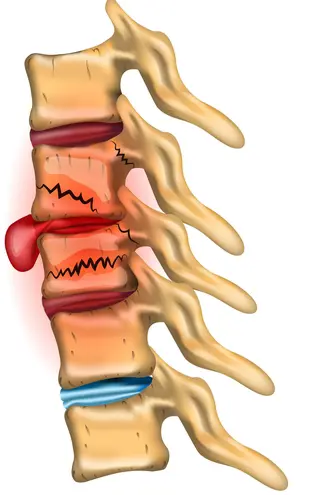

Заболевания позвоночника у домашних животных: диагностика и лечение